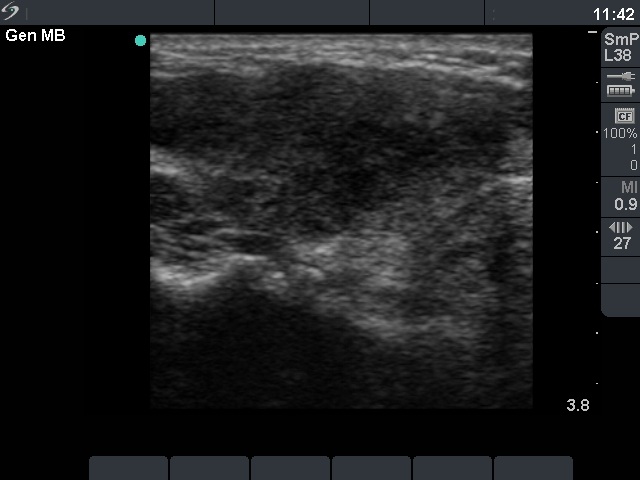

Ultrasonography: diffusely moderately hypoechogenic lobes with several circumscribed, even more hypoechogenic areas with blurred borders.